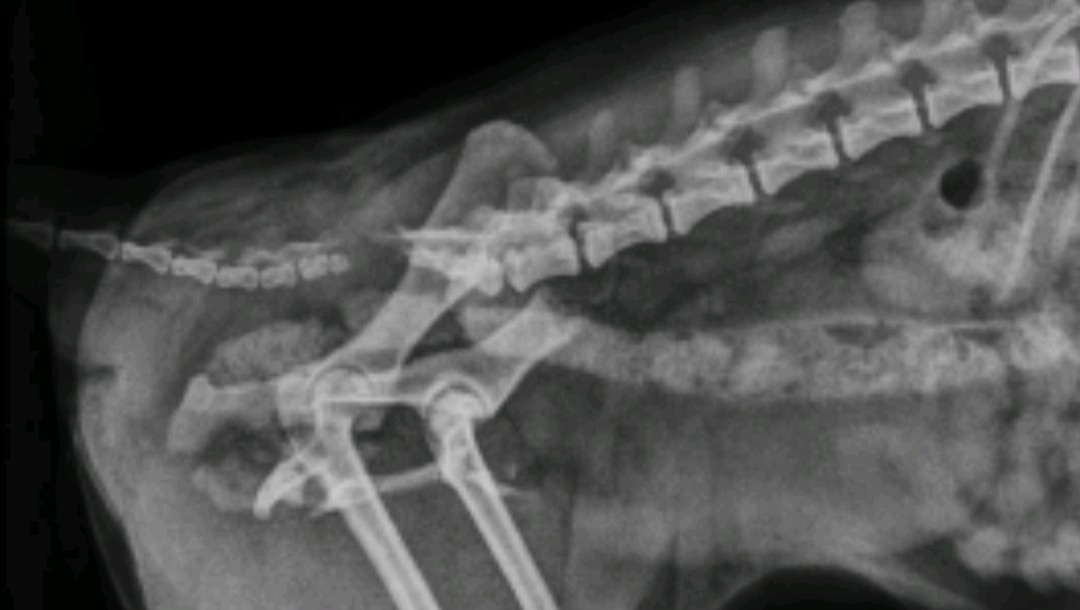

Als unser lieber Hund Maly 5 1/2 j.a. Pomeranian am 22.09.2024 ein Autounfall gehabt hat, haben die Tierärzte von Todesspritze für Maly auch gesprochen. Das könnten wir uns absolut nicht vorstellen und wollten nicht zulassen. In Folge des Unfalls erlitt Maly Beckentrümmerbruch, Schwanzabriss, innere Verletzungen, Alpträume

... Nach 21 Tagen in der Tierklinik Hofheim wurde Maly entlassen zur weiteren Behandlung ambulant und Physiotherapie. Von Monat zu Monat geht es Maly etwas besser, jedoch die Behandlungen werden noch etwas dauern. Leider war Maly damals, als der Unfall passiert nicht krank versichert. Jetzige Hundeversicherung übernimmt auch keine eventuellen weiteren Operationen, die mit diesem Unfall zusammen verbunden sein werden. Schön dass es Menschen gibt, die andere Wesen in ihrem Schicksal unterstützen. Ich gehöre auch zu diesem Kreis.